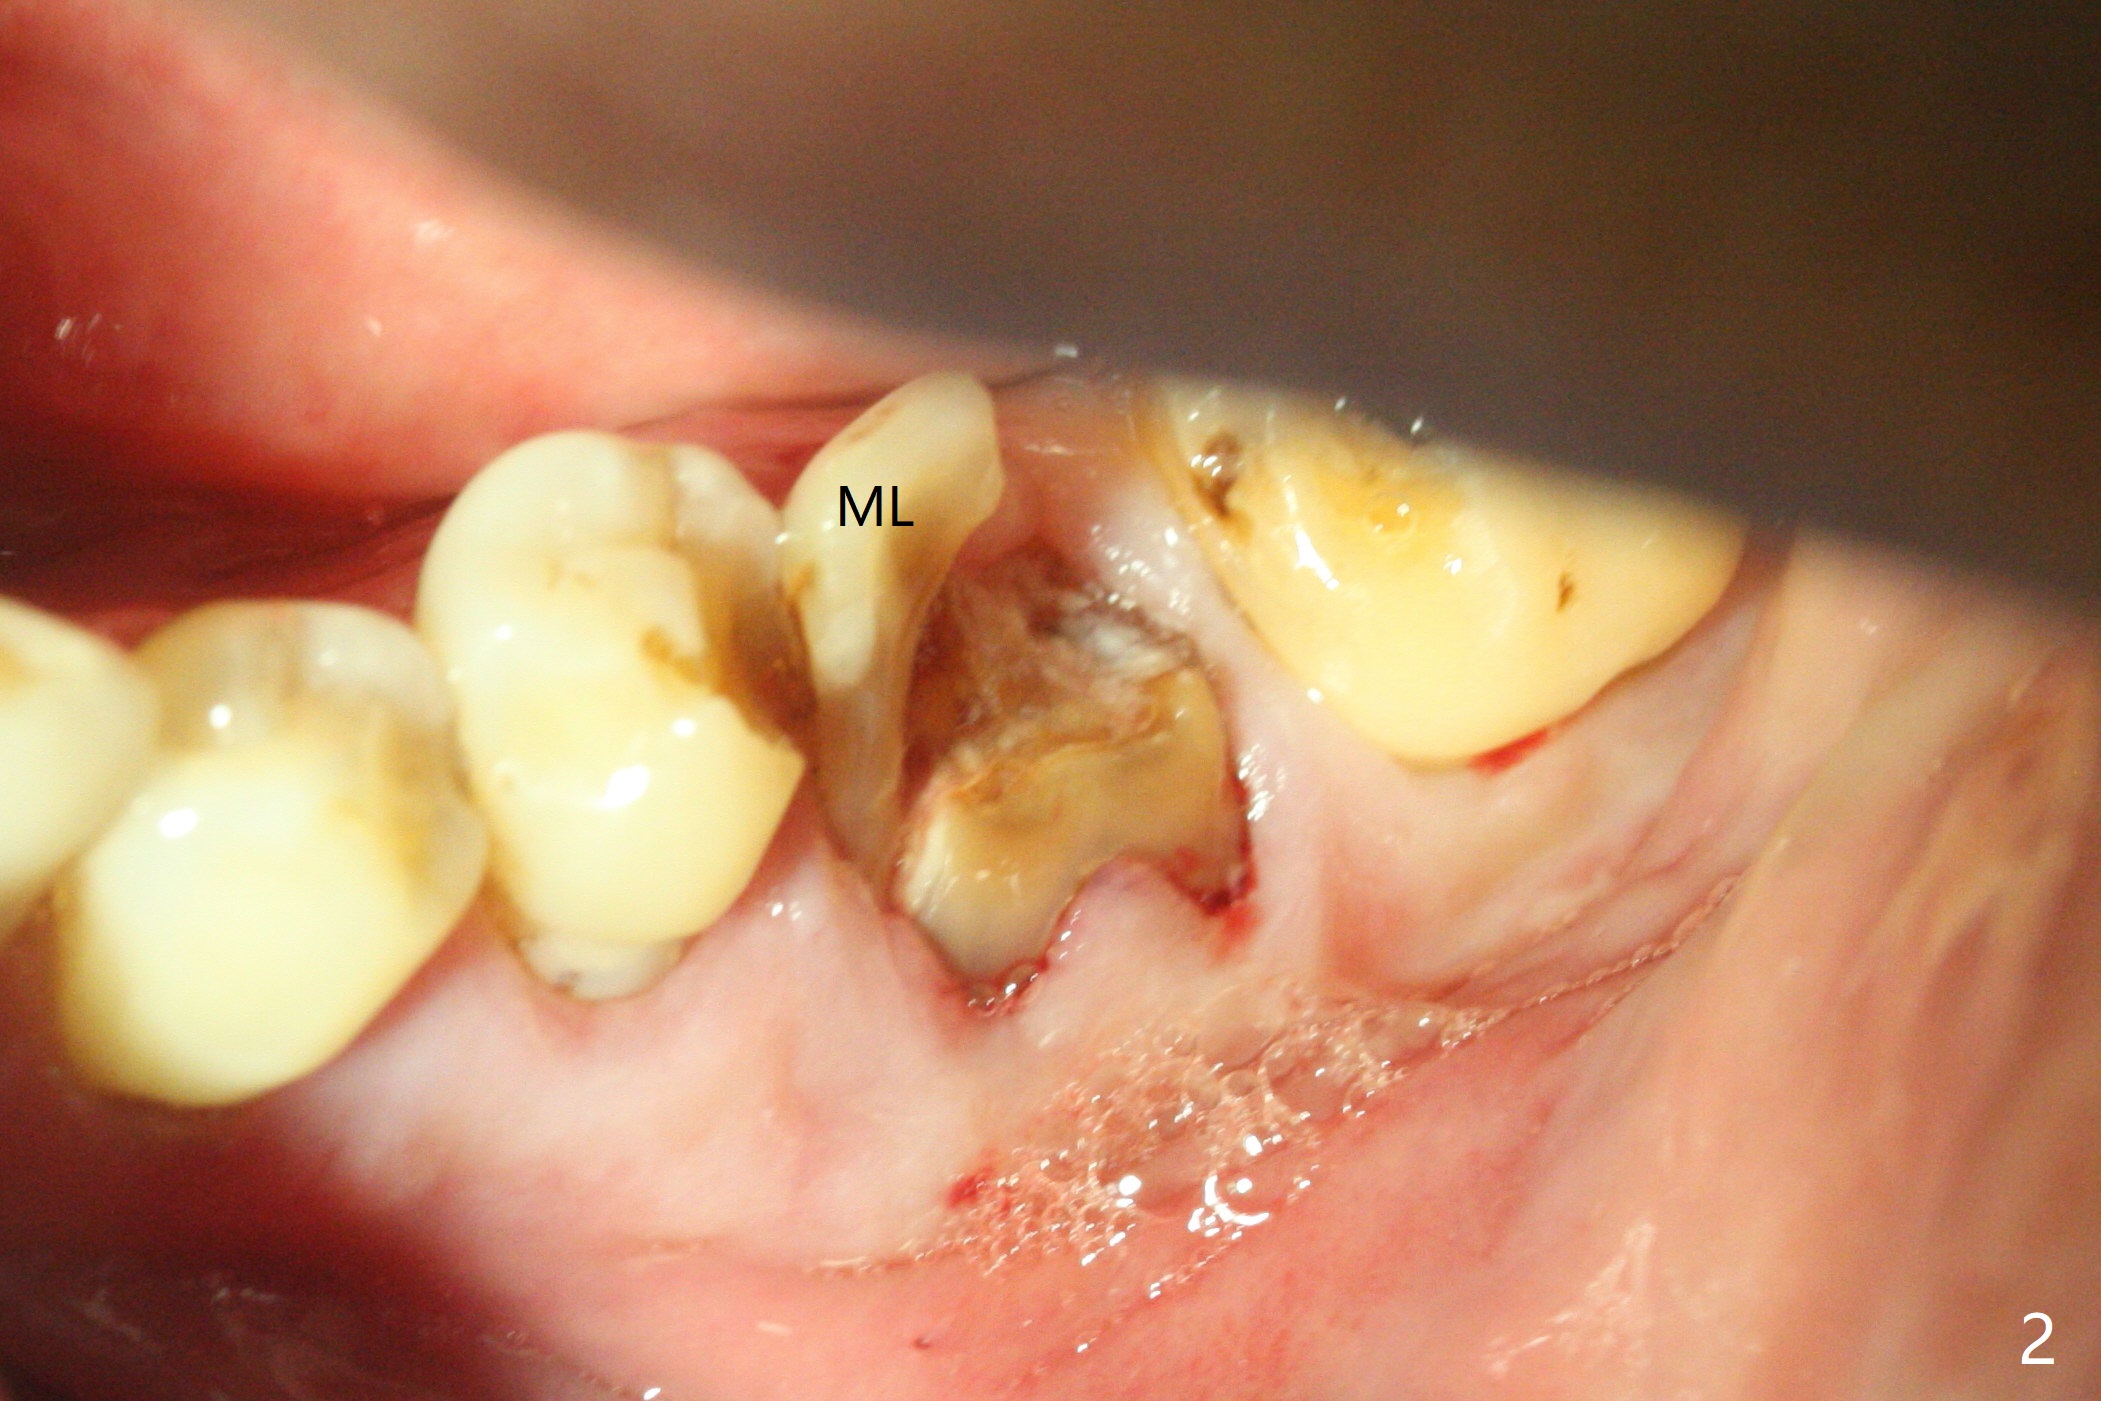

A 73-year-old man (with history of lung cancer with chemotherapy 6 years ago) requests removing the tooth #19 (Fig.1) with the loose mesiolingual fragment (Fig.2 ML). The mesiobuccal plate is low when the tooth is extracted. The septum should provide additional blood supply to bone graft to facilitate healing (Fig.3 S, as compared to the case without it). After placement of 6-month membrane and suturing, acrylic dressing is applied, which is stable 9 days postop (Fig.4 A). The acrylic dressing remains in place 1 month postop (Fig.5). After wiggling, it dislodges fairly easily. The socket heals with slight atrophy (Fig.6).